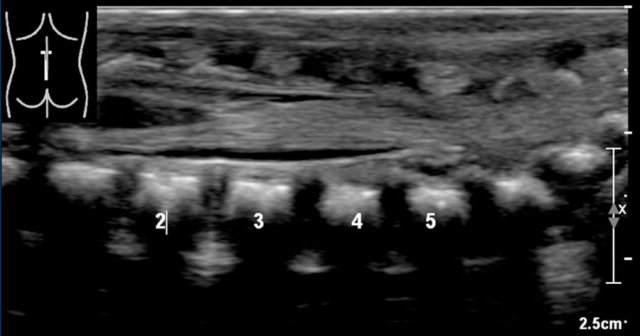

Position of the conus medullaris

The normal position of the conus is at L!.

It should not be below L2.

The best way to determine the position of the conus medullaris is by identifying the lumbosacral junction at the lordotic angle between the lumbar and sacral vertebrae (arrow).

It can be helpful to flex and extend the pelvis to see the point of motion of the sacrum.

In this newborn the lumbosacral junction is less clearly seen because there is no acute angle.

The numbers that we've put in, might be wrong.

If one is uncertain, make a panoramic or dual image of the lumbosacral vertebral column and compare the vertebral count from below upwards with a lateral plain film.